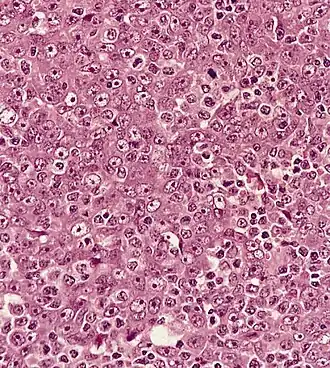

Назофарингеальная карцинома (рак носоглотки) — злокачественная опухоль, развивающаяся в верхней части глотки и значительно отличающаяся от других типов опухолей головы и шеи по своему развитию, причинам, клиническому течению и лечебной тактике. Повышенная заболеваемость отмечена в некоторых регионах восточной Азии и Африки.[2]